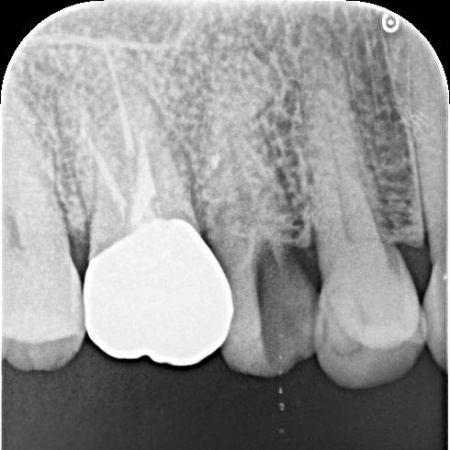

レントゲンを撮り詳しく確認したところ、過去に根管治療が施されていたものの、根の中に薬がしっかりと詰められておらず治療が不十分な状態でした。そのため、根管から歯根を覆う歯根膜が細菌感染して炎症を起こす慢性歯根膜炎が生じています。

根管治療とは、歯の神経を除去し神経が通っている根管を洗浄・消毒する治療です。

このまま放置すると細菌感染がさらに進行し、歯根周囲の骨が破壊されたり膿んだりして最終的に歯を失うおそれがあるため、早急な治療が必要と診断しました。

まず根管を丁寧に洗浄・消毒し、MTAセメントを用いて根の先端まで隙間なく密封しました。